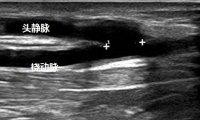

北京清华长庚医院肾内科(通讯员李敏侠、李月红)有些肾脏病患者最终需要透析治疗,我国目前有30多万血液透析患者,自体动静脉内瘘是最理想的透析通路。自体动静脉内瘘是将头静脉与桡动脉端侧吻合,使静脉里流着动脉血,静脉动脉化利于穿刺,保证足够的透析血流量。良好的动脉和静脉血管条件是动静脉内瘘成功建立的前提。人体血管资源有限,随着透析时间的延长,血管通路成为透析患者长期生存的制约因素。除了先天性因素外,抽血、输液、化疗药、中心静脉导管、套管针的放置都可能使上肢静脉受损,引起静脉炎和血栓形成,甚至静脉完全闭塞,肾脏病患者的血管保护应引起各科医护和患者的重视。

2.尽可能选用手背静脉或肢体远端血管,避免在同一部位反复穿刺,尤其是头静脉、肘正中静脉,避免对血管刺激较大的药物;

3.尽可能缩短静脉套管针留置时间,尽量放置于手背而不是头静脉;